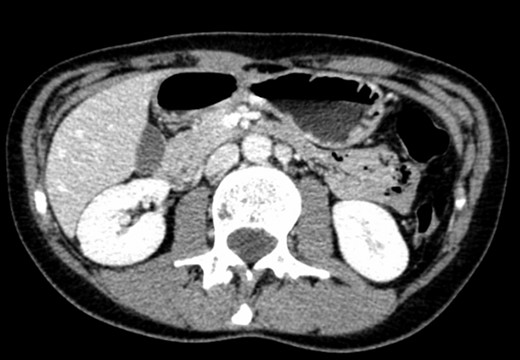

A 39-year-old Caucasian female patient presented to a General surgery outpatient clinic with complaints of epigastric pain, nausea, vomiting and weight loss for more than 5 years. The pain was worse after eating and with supine position. Vomiting was usually initiated 3–4 h after meals and consisted of undigested food. She had no significant prior medical history. On examination, the patient was extremely emaciated, with normal vital signs but with a distended abdomen and fullness over the epigastrium. She had already done an upper endoscopy that only showed gastric stasis. Abdominal ultrasound revealed a reduced angle between the AA and SMA (Fig. 1). An upper GI contrast study was requested, which revealed a distended stomach with delayed gastric emptying and lagging of contrast at the third portion of the duodenum (Fig. 2). Abdominal computed tomography (CT) scan was then performed. It demonstrated a severe distension of the stomach and proximal portions of the duodenum with constriction of the third part of the duodenum between the AA and SMA, with a reduced angle (11°) and shortened distance (4–5 mm) between these two arteries (Figs 3 and 4). These findings were suggestive of an aortomesenteric clamp. Hence, based on known findings, the diagnosis of Wilkie’s syndrome was established.

CT scan—sagittal CT image of reduced angle between AAA and SMA.

CT scan—axial CT image of obstruction of the third portion of duodenum between AAA and SMA.